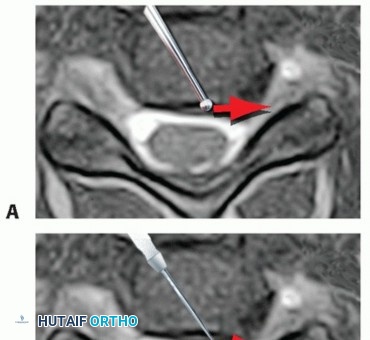

### TECH FIG 4 • A,B. Removing herniated nucleus pulposus. A. With extruded herniations, a rent in the longitudinal fibers of the PLL may be identified. A curette is then used to delineate the edges of the rent in the PLL. Once this is defined and the surgeon is certain of a plane between the PLL and underlying dura, a Kerrison is used to enlarge the edges of the rent. B. The rent has been enlarged to provide more room for finding the herniation. Curettes are then used to fish out the fragments and decompress the cord or root. C,D. Removing the PLL. C. If the PLL is intact, it can be removed by teasing in between the longitudinal fibers with a microcurette. Once a plane is established, a Kerrison can be used to remove the PLL. D. It is often easier to find this plane in the central portion of the PLL, where it is thicker, than laterally, where it is thinner and less defined. By delicately probing with a microcurette, the extruded fragment can be fished out from behind the PLL. If necessary, the defect in the PLL should be enlarged with a 2-mm Kerrison until a satisfactory portal is available to remove the herniation and ensure that all loose disc fragments have been removed. It is debatable whether the PLL needs to be resected in every case. In general, we prefer to do so, especially in cases of disc extrusion, and do not consider the decompression complete until the dural sac or exiting nerve root (depending on which is compressed based on preoperative imaging) is inspected for the absence of any further compression. If, however, the compressive lesion is an uncinate spur, with no evidence of subligamentous disc extrusion, satisfactory decompression can be achieved by removing the spurs without necessarily removing the PLL. If there is no rent in the PLL, one can be created by teasing a microcurette between the longitudinal fibers of the PLL until the curette is posterior to the PLL (TECH FIG 4C,D). Once the plane is identified between the PLL and dura, the fibers of the PLL can be resected with a curette or Kerrison rongeur. 6 Placing tension on the PLL with gentle distraction will facilitate its removal. We generally find it easier to define a plane in the PLL centrally, where it tends to be thicker, than laterally, where it is thinner and the plane with the dura is less distinct. Often, there are multiple layers of PLL, and usually in chronic cases, there is a membranous layer between the PLL and the dural sac that can be confused with dura itself. In general, if it does not look like dura, it probably is not. The portion of the PLL contralateral to the disc herniation or symptomatic foraminal stenosis does not routinely need to be removed. ### Avoiding Vertebral Artery and Neural Injury Before surgery, the surgeon should always scrutinize the position of the vertebral arteries on the preoperative scans to rule out the presence of aberrancies in their course (TECH FIG 5). Aberrations typically occur within the vertebral body. However, it is not uncommon for one vertebral artery to be closer to the uncinate on one side versus the other, which would mandate greater caution when approaching that side.3 In the absence of vertebral artery aberrancy, laceration to the vertebral artery is most likely to occur from the surgeon's loss of orientation to the uncinates. The uncinates define the safe zone for the vertebral artery and the effective zone for the decompression. It is imperative to define and maintain orientation with both uncinates at all times during anterior cervical surgery.

TECH FIG 5 • A,B. Vertebral artery anomalies. A. The right transverse foramen (arrow) courses somewhat more medially than the one on the left. This is a subtle but potentially important anomaly to observe preoperatively. B. The anomaly occurs within the vertebral body rather than at the disc space level where the right transverse foramen is now more normally positioned (arrow). C. Penfield lateral to the uncinate. In certain cases, especially if there is a deformity, the location of the lateral border of the uncinate (ie, the safe zone for the vertebral artery) may not be obvious after elevation of the longus colli. Placing a Penfield dissector no. 4 gently underneath the longus colli, retracting it laterally, and then hooking the dissector lateral to the uncinate will allow for safe orientation to the vertebral artery. The vertebral artery is typically in the anterior two-thirds of the disc space. When curetting disc material in this area, a vertebral artery laceration might occur if the curette strays lateral to the lateral border of the uncinate. If in doubt, a Penfield dissector can be used to identify the lateral border of the uncinate processes to avoid straying laterally and injuring the vertebral arteries, which are generally a few millimeters from the lateral edge of the uncinate (TECH FIG 5C). ### Graft Sizing and Placement Ultimate graft height can be estimated preoperatively from the preoperative lateral film. In many cases, a graft height of 2 to 3 mm more than that measured on the preoperative lateral film will be the optimal choice. Ideally, the anteroposterior depth of the graft should be a few millimeters less than that of the disc space, such that the graft can be countersunk 2 mm without entering the spinal canal. The final height of the graft can be determined after endplate preparation with sizers that accompany commercial grafts (TECH FIG 6). The trials should be lightly malleted into position under gentle Caspar pin distraction. A snug fit in the distracted position will ensure an excellent fit after removal of distraction pins. If the trial does not fit but the next smaller trial seems too loose, the surgeon should identify the area of impingement and lightly decorticate that area. Then, the trial is reinserted. For multilevel ACDF, we prefer to decompress and graft each segment before proceeding to the next level. One way to enhance fusion rates is to place as much bone into the interspace as possible. A wide decompression also provides greater room for bone graft. Space lateral to the structural bone graft in the uncinate regions can be packed with bone or bone graft substitutes. 7 If the space is wide enough, two grafts can be placed side by side to fill the entire space.